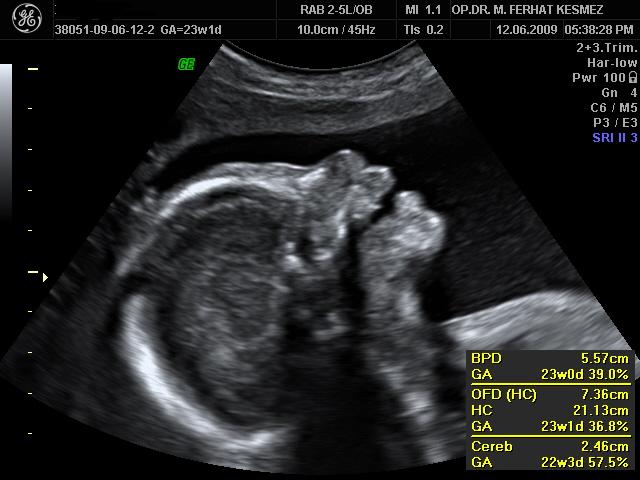

Op. Dr. Muhammed Ferhat Kesmez

Kadın Hastalıkları, Doğum ve Tüp Bebek Uzmanı

• Op. Dr. Muhammed Ferhat Kesmez, kadın sağlığı, gebelik takibi, doğum ve tüp bebek tedavisi alanlarında uzmanlaşmış deneyimli bir hekimdir. Kısırlık (infertilite) tedavisinde en son teknolojileri kullanarak çiftlere anne-baba olma yolculuklarında rehberlik eder. Bireysel ve bilimsel yaklaşımlarla hastalarına özel tedavi yöntemleri sunarak sağlıklı gebelik süreçleri sağlamayı hedefler. Güvenilir ve hasta odaklı hizmet anlayışıyla, modern tıbbın sunduğu yenilikleri hastalarına ulaştırmaktadır.